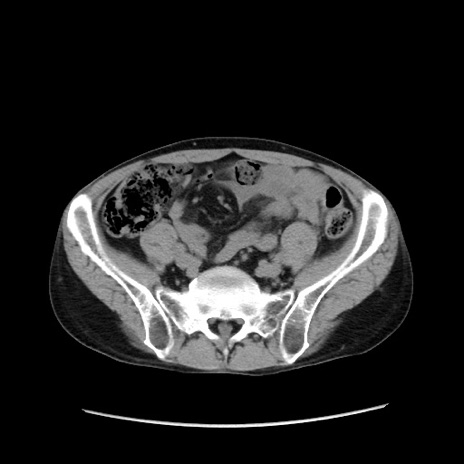

症例37(横断像)

【症例】40歳代 男性

【主訴】腹痛

【現病歴】4時間ほど前に電車に乗車中に臍部上より腹痛出現。徐々に増悪し起立困難となり、救急外来受診。生ものは数日食べていない。今朝お雑煮を食べた。

【身体所見】BT 36.8℃、BP 117/84mmHg、HR 91/min、SpO2 97%、苦悶様、腹部:臍上部広範囲圧痛あり、反跳痛±

【データ】WBC 8100、CRP 0.03